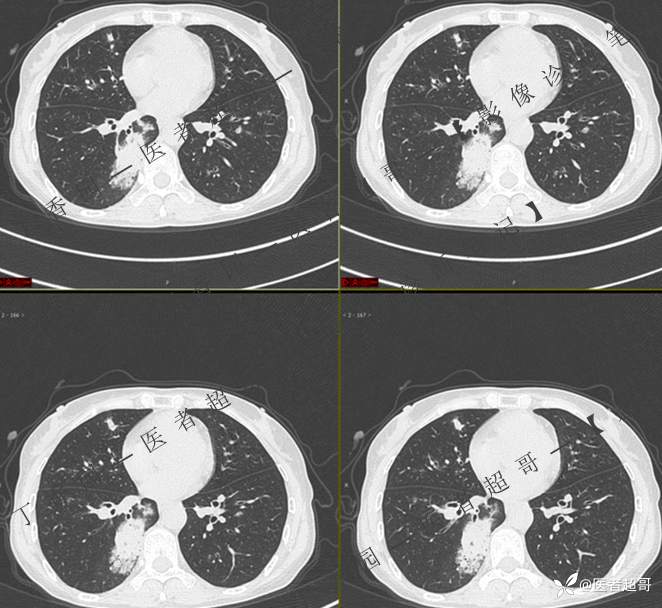

临床治疗一周后复查

第二次检查